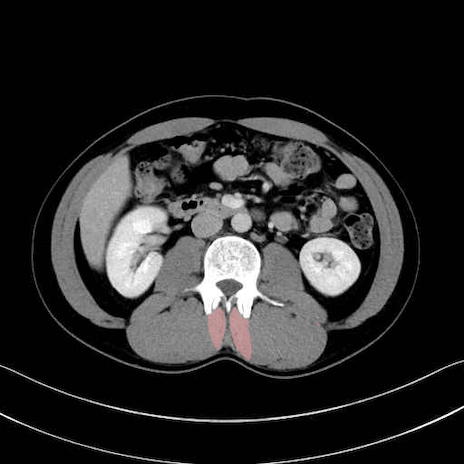

多裂筋 (Multifidus)